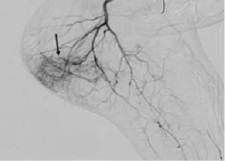

- Image-guided heel pain treatment using fluoroscopy or ultrasound.

- Embolic injection to block the blood vessels causing inflammation in the plantar fascia.